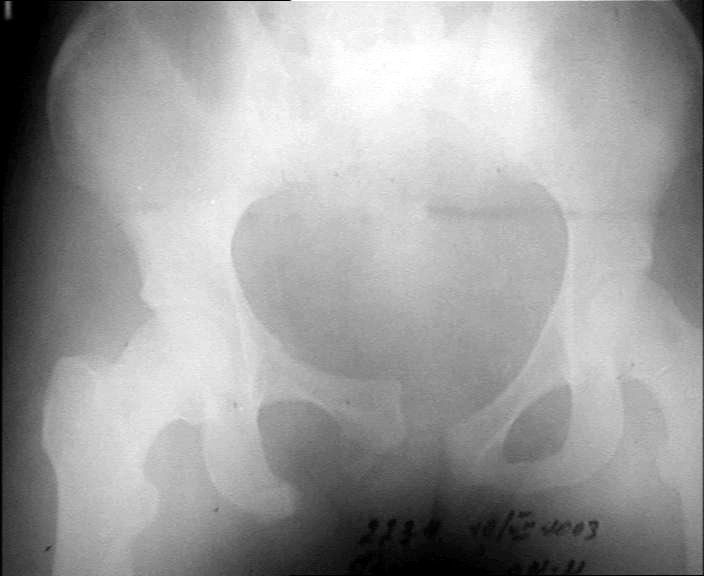

Больной 20 лет. Автодорожная авария 06.07.03.

Диагноз : оскольчатый сегментарный перелом правого бедра. Перелом лобковой кости со смещением, разрыв лобкового сращения.Планируем остеосинтез бедра пластиной. (гвоздей с блокировкой нет). Сшивание симфиза.Как поступить с переломами лобковой кости? Сергей ЗыряновНСО г. Куйбышев

Такое смещение в переднем отделе невозможно без повреждения задних отделов, а стабильность таза в основном они и обеспечивают. Что-то там неладно в области правого крестцово-подвздошного, и смещение по вертикали есть. Снимки плохого качества, трудно разглядеть, на перелом крестца похоже. Сдлать бы еще и inlet, то есть фас с направлением луча с краниальной стороны градусов 30-40 от вертикали.